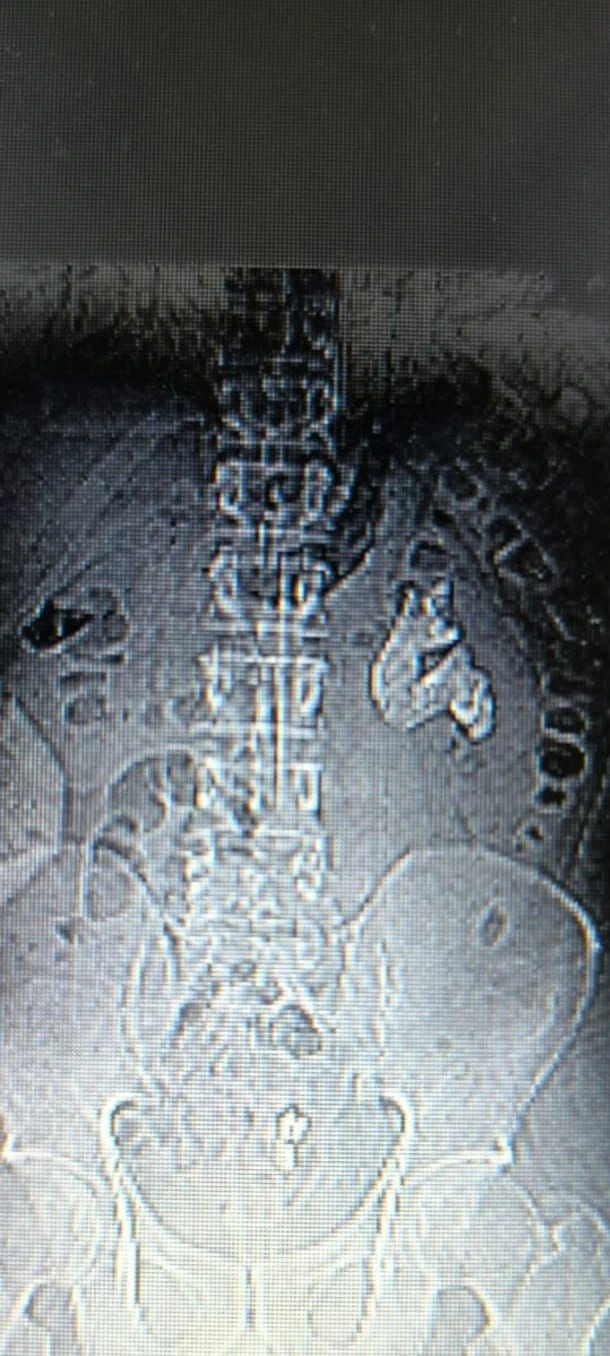

Tedavi sürecinde yapılan Bilgisayarlı Tomografi (BT) görüntülemesinde, böbreğin tamamını kaplayan, sert yapıda (950-1450 HU), tıp literatüründe “staghorn”, halk arasında ise “geyik boynuzu taşı” olarak bilinen büyük bir böbrek taşı tespit edildi. Bu tür taşların, böbreğin tüm boşluklarını doldurarak tekrarlayan enfeksiyonlara ve uzun vadede böbrek fonksiyon kaybına yol açabildiği belirtildi.

Operasyonu gerçekleştiren Üroloji Uzmanı Dr. Miraç Ataman, staghorn taşların tedavisinin hayati önem taşıdığını vurgulayarak, vakada Perkütan Nefrolitotomi (PCNL) yöntemini uyguladıklarını ifade etti. Dr. Ataman, PCNL yönteminin özellikle 2 santimetreden büyük ve kompleks böbrek taşlarında altın standart kabul edildiğini belirtti.

Normal şartlarda staghorn taşların temizlenmesinin uzun sürebildiğini ve çoğu zaman birden fazla seans gerektirdiğini dile getiren Dr. Ataman, ameliyat ekibinin deneyimi ve hastanenin modern altyapısı sayesinde ciltten tek giriş yolu açılarak yaklaşık 1,5 saatlik tek seansta böbreğin tüm taş yükünün başarıyla temizlendiğini açıkladı.